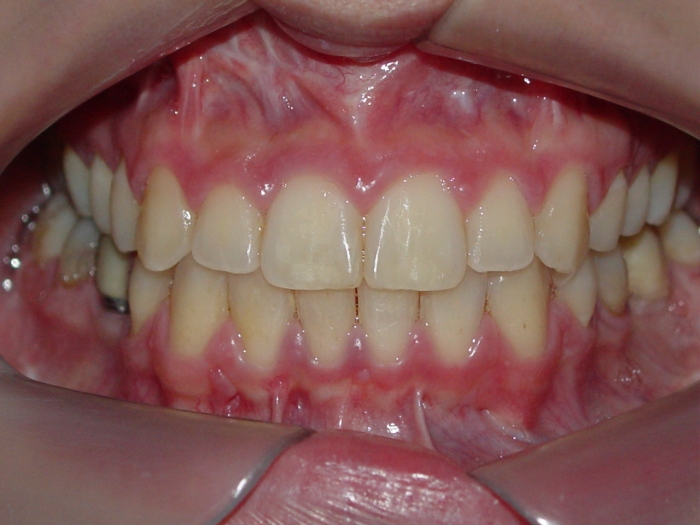

Mordida inicial

Mordida final